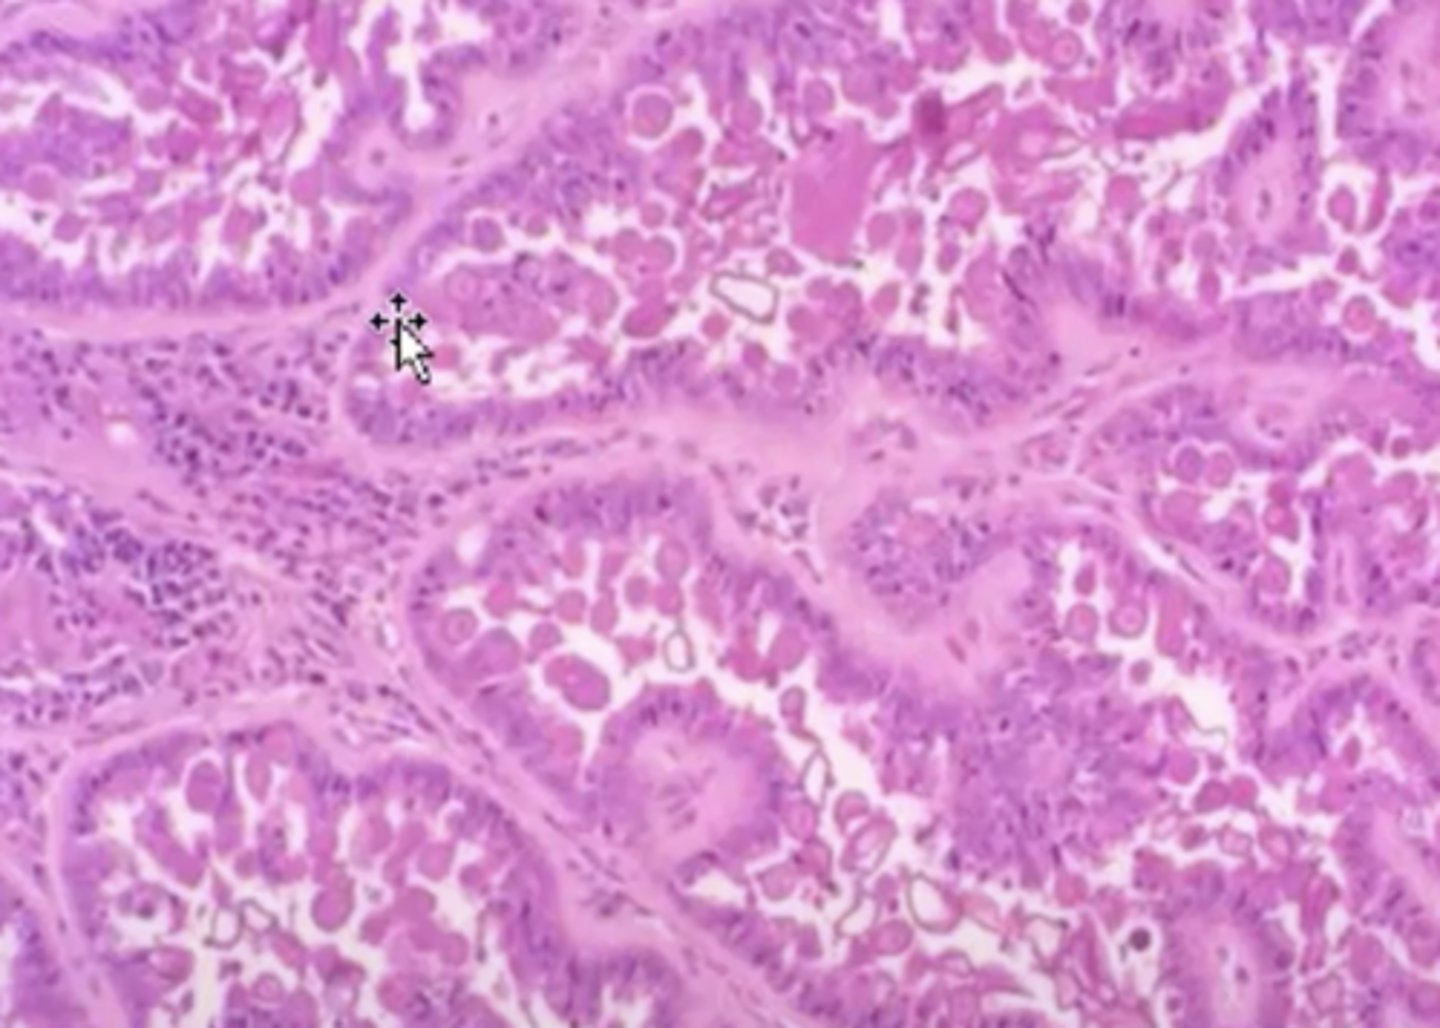

adenocarcinoma

-malignant tumor of epithelial origin

-tubular patterns on histopath

What kind of tumor is this?